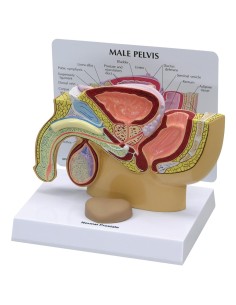

Pelvis masculin 3B Scientifique avec ligaments, vaisseaux, nerfs, plancher pelvien et...